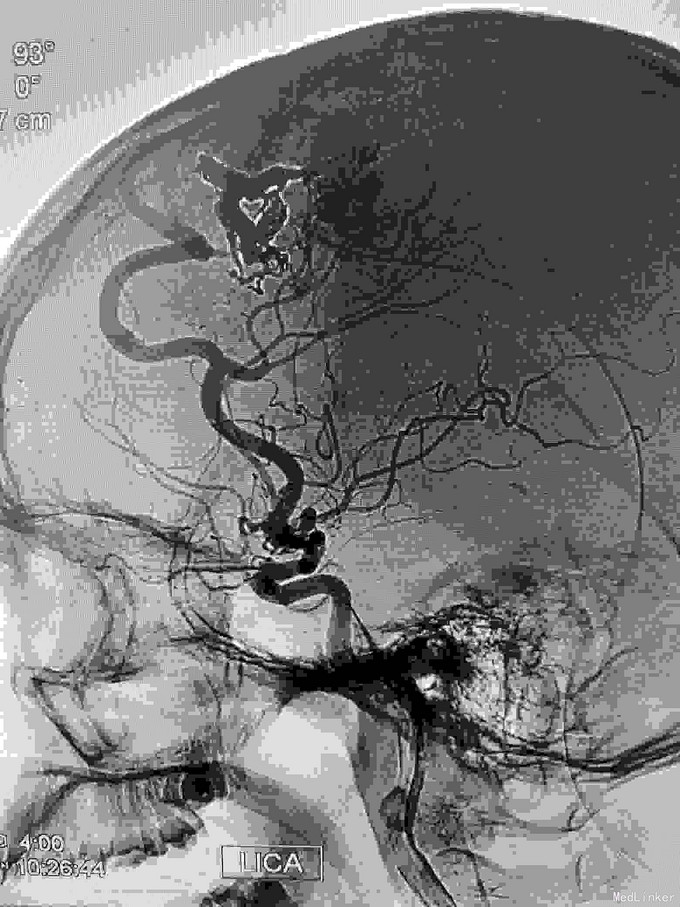

右额AVM

男,23岁。右额AVM。分次治疗。